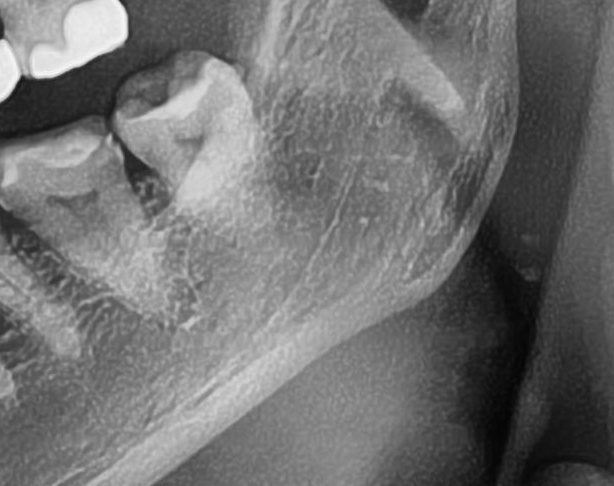

次に3番目の患者様。

左下の親知らずに入れていた詰め物が外れたため、今回抜歯することになりました。

頭もしっかり出ている状態でまっすぐに生えていたので、あっという間に抜歯終了。